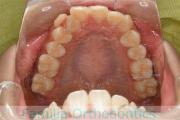

上顎

下顎